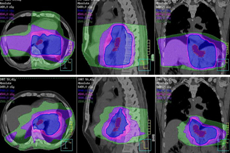

食道IMRT放射治療